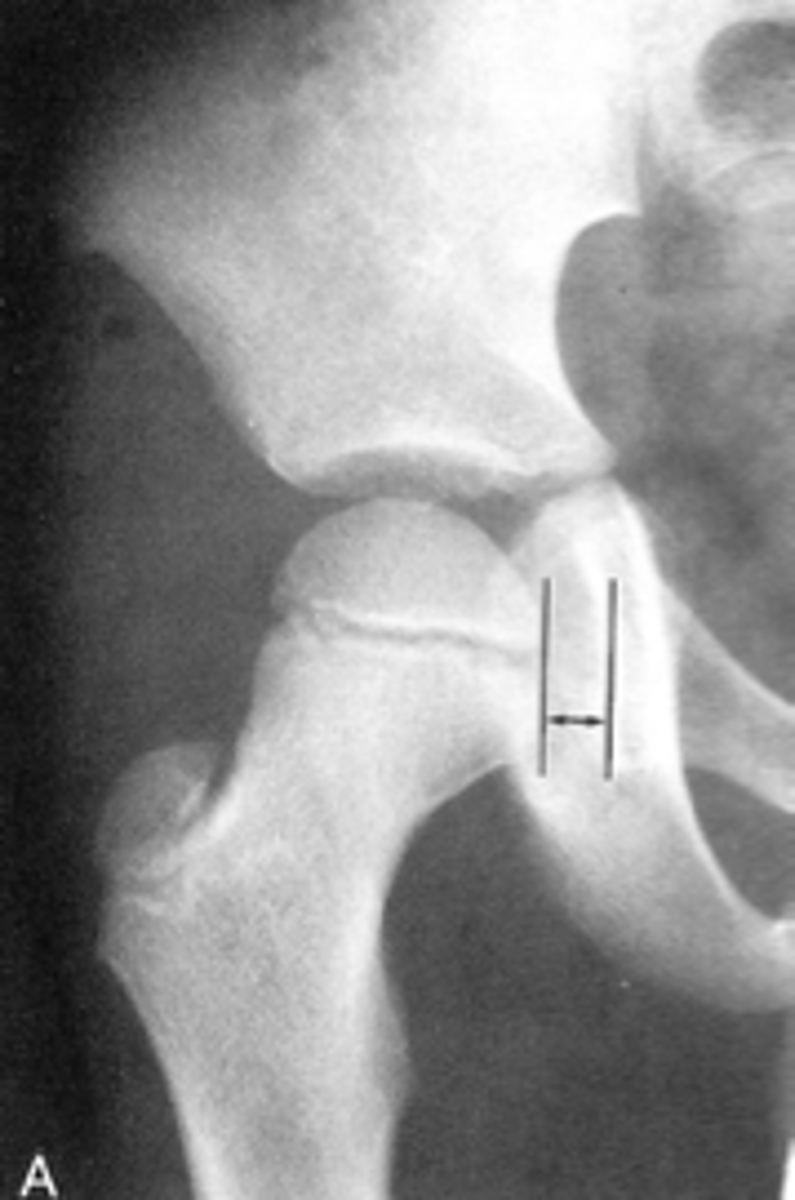

Shenton's line

ID measurement

<p>ID measurement</p>

- AP hip

- AP pelvis

What views are used to see Shenton's line?

- Smooth arc along femoral neck

- Obturator foramen

Shenton's line landmarks

<p>Shenton's line landmarks</p>

Continuous and smooth

Shenton's line normal measurements

<p>Shenton's line normal measurements</p>

- Hip dislocation

- Femoral neck fracture

- Slipped epiphysis

Clinical significance of Shenton's line

<p>Clinical significance of Shenton's line</p>